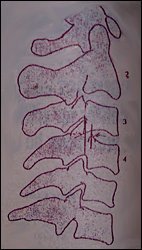

Subluxations associated with trauma consists of minor forward or backward displacement of one vertebra on another. Harris lists subluxation under stable cervical injuries of the spine.1 According to Jackson2 subluxations can be noted on lateral views of the cervical spine and many times are accentuated in flexion and extension views. The backward subluxations (retrolisthesis subluxations) are present when the posterior margin of the vertebral body which is displaced posteriorly is seen to lie behind the posterior margin of the adjacent distal vertebral body. The superior facets of the lower vertebra can be displaced forward enough to encroach on the intervertebral foramina (Figure 1).

Figure 1: Backward subluxation or retrolisthesis subluxation